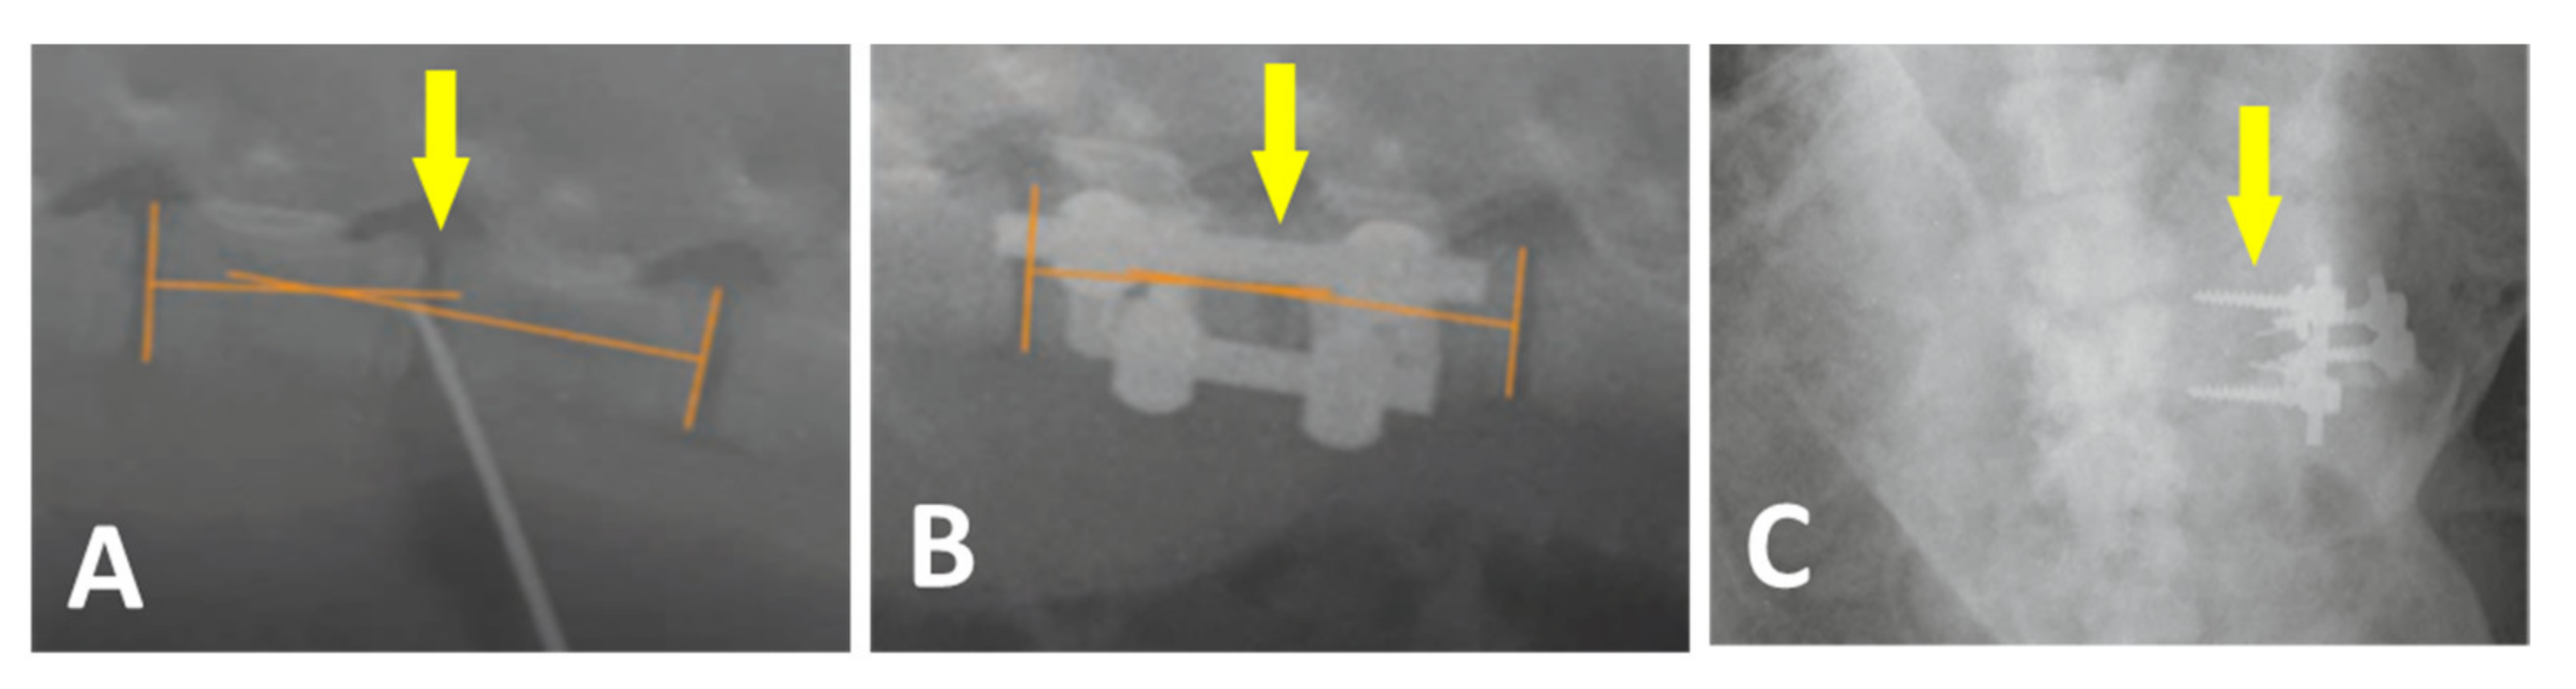

Plain radiographs were regularly repeated before and after the surgery as depicted in Figure 6A,B, respectively.

Figure 6.

Plain X-ray radiographs of lateral views taken before (A) and after the surgery (B) Yellow arrows show the L2/L3 segment of implantation. Loosening and migration of the screws of the A2 group in 4 weeks after surgery. Plain X-ray radiographs of the antero-posterior view (C).

All 24 pigs recovered from the surgery without unusual events. One pig from group A2 showed loosening and migration of the screws observed on X-ray 4 weeks after surgery (Figure 6C). Regarding this animal, no clinical related manifestation was noted. No other hardware problems with the plate-screw-tube construct on regular X-ray examination were detected. No general intraoperative, early, or late postoperative complications were observed.